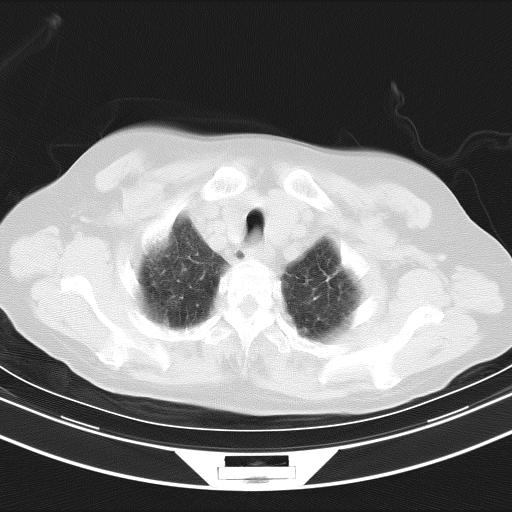

老年女性,嗜睡3天,意识模糊。轻咳,无发热。

两肺慢支炎伴感染,左侧胸腔积液。纵膈及双侧肺门淋巴结肿大建议复查。

双肺多发淡片影,毛玻璃影,,支持支气管肺炎,,建议血气找原因,,嗜睡是否肺性脑病?有没有慢支病史?

1)两肺感染性病变;建议抗炎治疗后复查。2)纵隔淋巴结肿大。3)左侧胸腔积液。